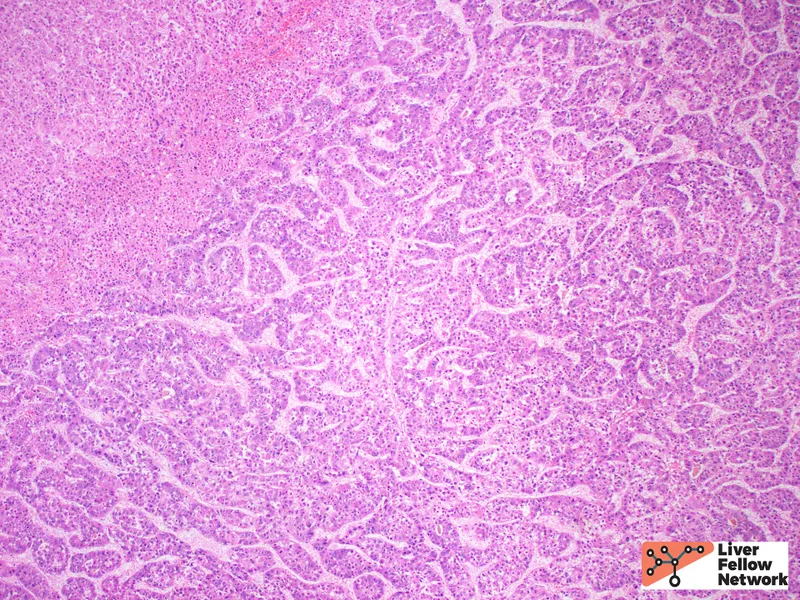

- Accelerated Fibrosis: Faster progression to cirrhosis, decompensated liver disease (ascites, encephalopathy), and hepatocellular carcinoma (HCC) compared to mono-infection.

- Co-infection with HBV and HCV dramatically accelerates progression to severe liver disease, including cirrhosis and hepatocellular carcinoma (HCC).